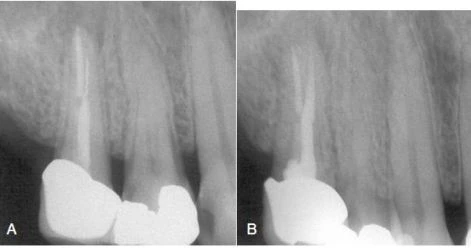

Hình 8. A, Dụng cụ gãy ở gần chóp của chân ngoài răng cối nhỏ hàm trên. B, Hoàn thành việc điều trị lại. Mảnh dụng cụ được băng qua bởi dụng cụ trâm tay và được lấy ra bởi tay siêu âm và trâm nội nha.

– Việc loại bỏ mảnh gãy dụng cụ nằm ở sâu vẫn có thể thực hiện bằng kỹ thuật siêu âm nếu có thể đưa dụng cụ băng qua mảnh gãy được. Hình 14-46 cho thấy lộ trình tháo mảnh gãy nằm sâu ở ống ngoài răng cối nhỏ hàm trên. May mắn là hình dạng ống tủy cho phép các trâm nhỏ băng qua mảnh gãy và cuối cùng mảnh gãy được tháo ra bởi một trâm nội nha và tay khoan siêu âm. Sau đó, việc điều trị tủy được tiến hành thành công. Điều đáng tiếc là nếu mảnh gãy nằm trong ống tủy có đường kính nhỏ hơn dụng cụ thì hiếm khi có thể đi băng qua mảnh gãy được. Việc dùng lực quay mạnh càng khiến cho dụng cụ dễ gãy hơn là cải thiện được tình hình.